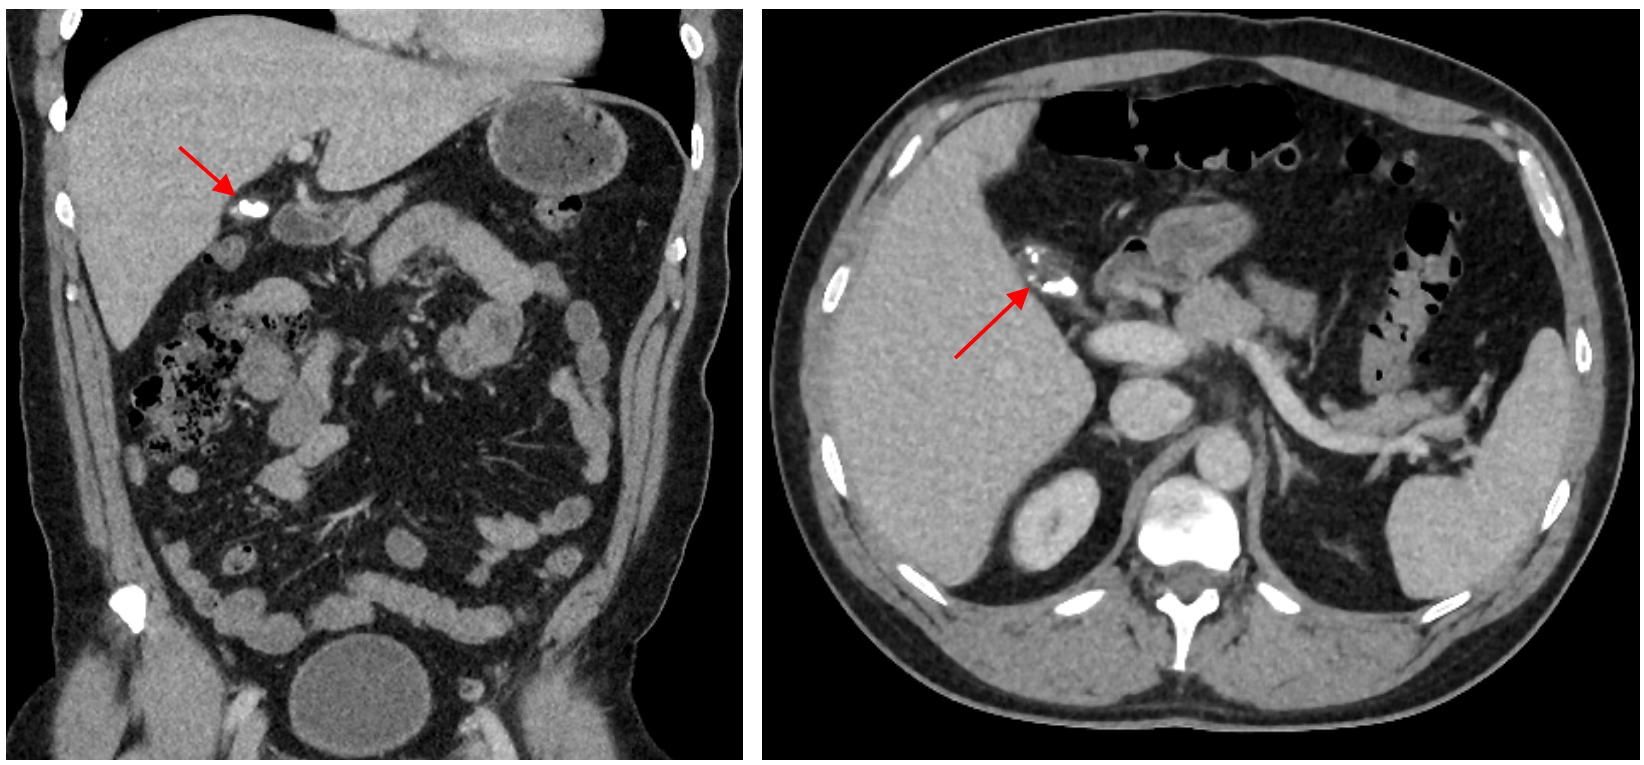

Initial computed tomography scan (CT) showed a thick-walled cystic structure containing stones in the gallbladder fossa which was indicative of chronic inflammation (Figure 1). Subsequent magnetic resonance cholangiopancreatography (MRCP) displayed evidence of a remnant gallbladder containing a 6-mm calculus (Figure 2). Patient was then scheduled for an elective robotic-assisted laparoscopic cholecystectomy for removal of the remnant gallbladder.

Physical examination and blood work narrow down the symptoms to hepatobiliary origin, but imaging allows for a definitive diagnosis to be made. If patients present to the emergency room, they may receive an abdominal CT scan as an initial study. This can display gallbladder dilation, gallbladder wall thickening, and radio-opaque stones.8,11,13 However, if cholecystitis is already suspected, an abdominal ultrasound may be used as a less expensive initial imaging study compared to CT scans. A study by Singh et al. demonstrated ultrasonography accurately identifying calculi in remnant gallbladders in 89% of their sample.14 However, in this study abdominal ultrasound failed to diagnose remnant gallbladder cholelithiasis in 11% of their patients. Similarly, Dikmen et al. displayed a failure to identify the remnant gallbladder in four (36.3%) of their eleven patients.12 The most definitive method of identifying the remnant gallbladder and surrounding anatomy is with an MRCP. In the study performed by Singh et al. MRCP was able to accurately diagnose remnant gallbladder calculi in all but two (4%) of the patients that underwent one.14 In our case, the patient presented to the emergency room initially, so he received a CT scan and an MRCP which led to the final diagnosis of remnant cholecystitis.